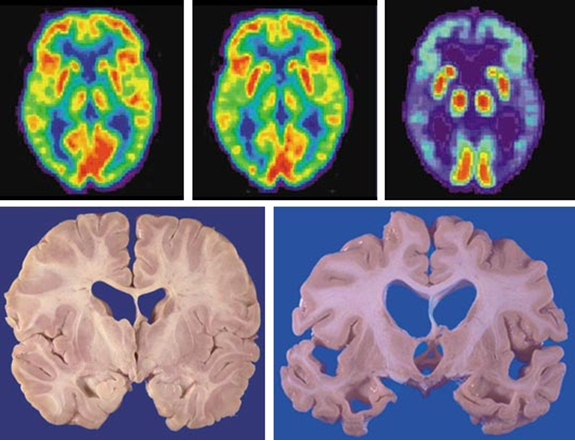

图2. 葡萄糖代谢脑成像(上)和脑切片(下)。左上:20岁的正常人;中上:80岁的正常人;右上:80岁的AD患者;左下:非AD患者;右下:AD患者